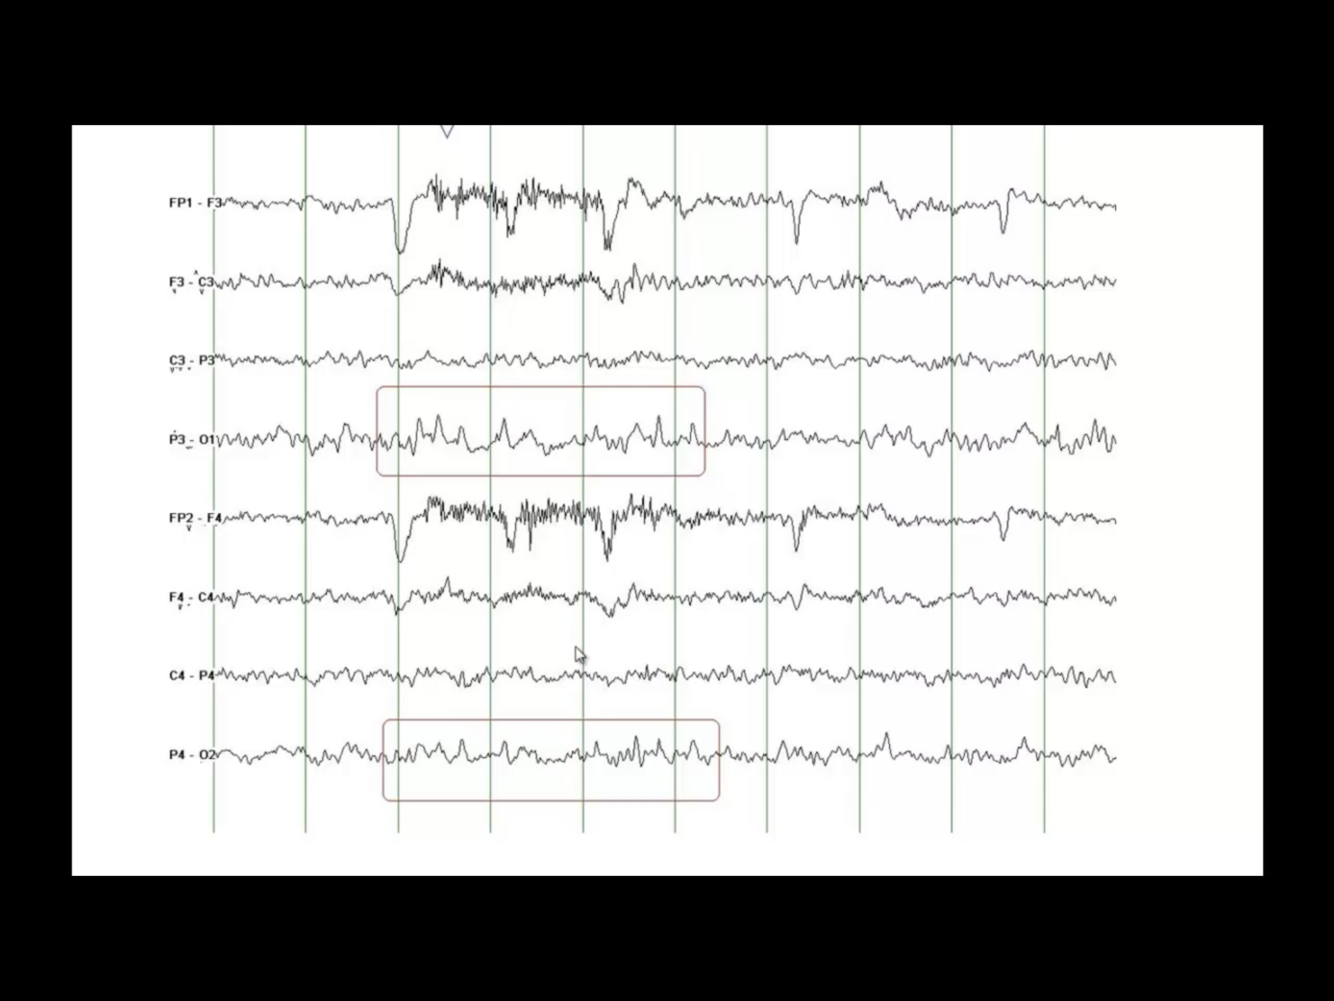

SREDA (Subclinical Rhythmic Electrographic Discharges in Adults))

• 5-6 Hz sharply contoured theta

• Diffuse but maximal over parietal and posterior temporal regions

• Seconds - 2 min (usually > 30 seconds)

• Drowsiness

• Usually abrupt onset and termination

• Hyperventilation can trigger

• Older adults (usually > 50 y/o)